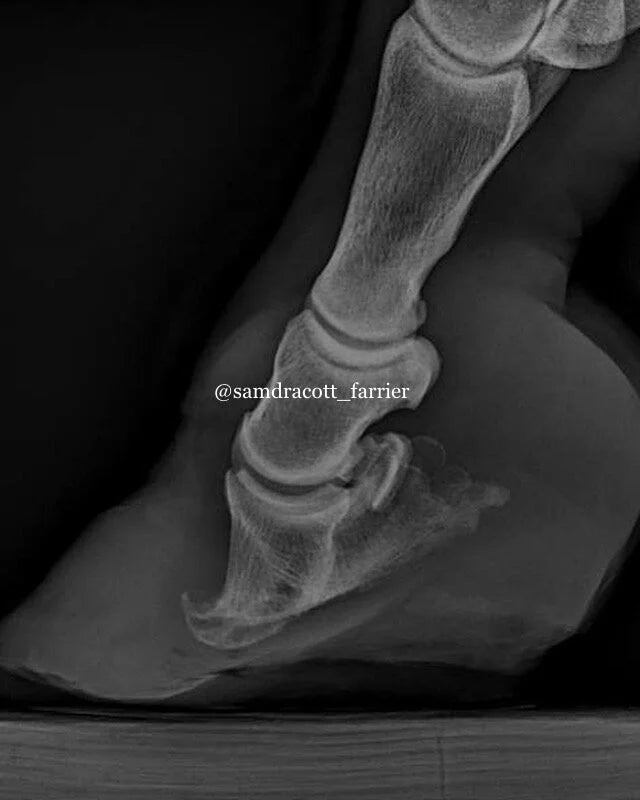

Remedial / Laminitic Shoeing

Laminitic Shoeing

Remedial Shoeing